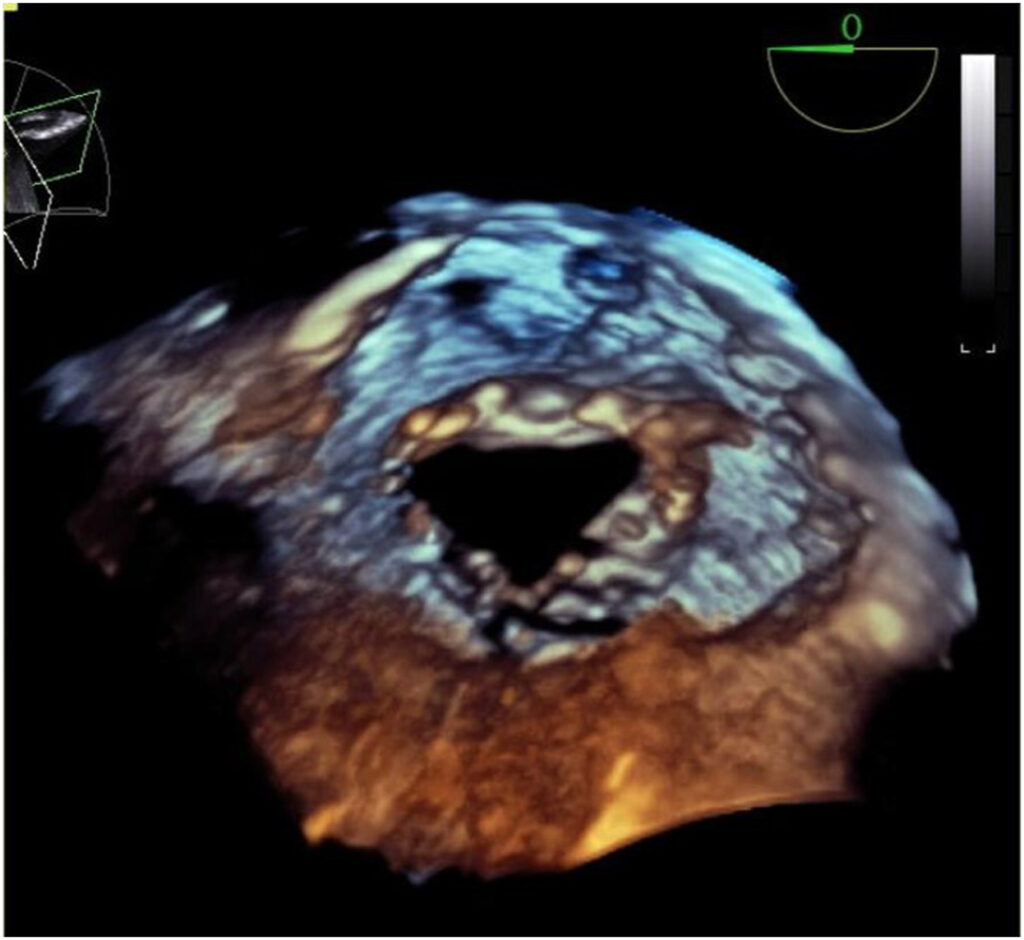

Ecocardiograma de 09 anos antes demonstrava apenas uma IMi discreta. O paciente foi submetido a estudo transesofágico cujo resultado mostrou uma VMi trivalvular com IMi importante originada de um folheto posterior dividido de forma assimétrica.

Dois músculos papilares foram observados em posições habituais e um pequeno folheto comissural com cordoalhas aderidas à ele foi identificado entre os dois folhetos posteriores .

Os achados, portanto, corroboraram a presença de uma comissura anatômica e uma VMi trivalvular congênita.